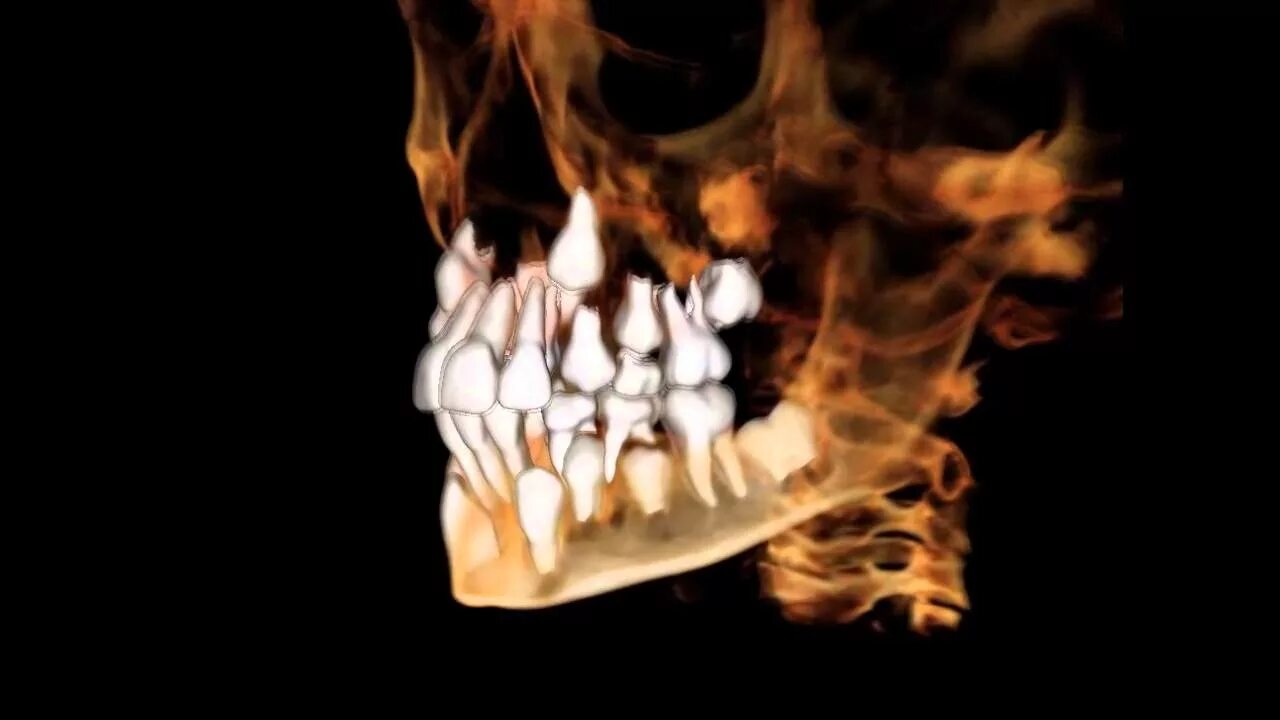

Матрица гаряева зубы и десна